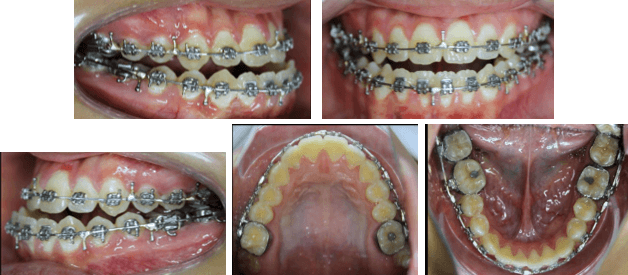

Fase Ortodoncia Post Quirúrgica y Finalización

En esta fase de Ortodoncia post quirúrgica donde se aprovecho el fenómeno de Aceleración Regional que se activa gracias a la cirugía ortognática y se lograron los objetivos oclusales, funcionales y estéticas en poco tiempo.

Fase de Finalización

• Paralelismo de raíces

• Detallado

• Elásticos Clase III

• Perfeccionamiento de los torques